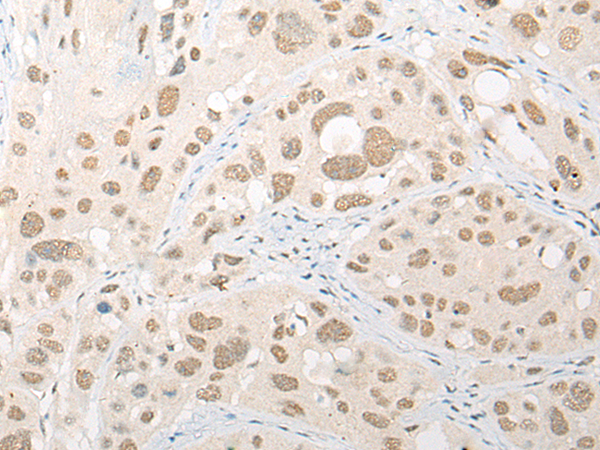

IHC positive control: |

Human esophagus cancer; Human ovarian cancer |